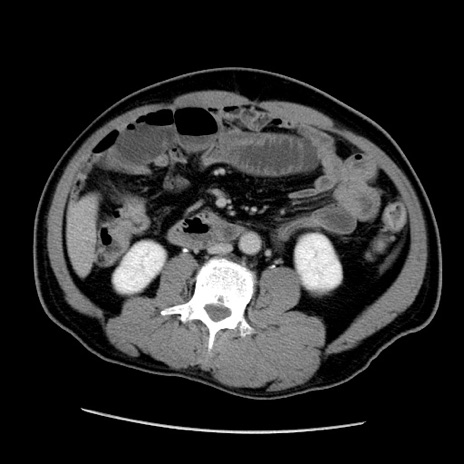

症例22(横断像)

【症例】50歳代男性

【主訴】腹痛

【現病歴】AVMからの被殻出血のため回復期リハ病棟入院中。 本日午後3時頃急に下腹部痛が出現した。

【既往歴】AVM、被殻出血、虫垂炎、高血圧

【身体所見】意識晴明、左半身不全麻痺、会話の理解は良好、36.5°C、腹部:膨隆、全体に板状硬、下腹部正中に圧痛点あり、反跳痛-、筋性防御不明、右下腹部にope scar

【データ】WBC 9400、CRP 0.06